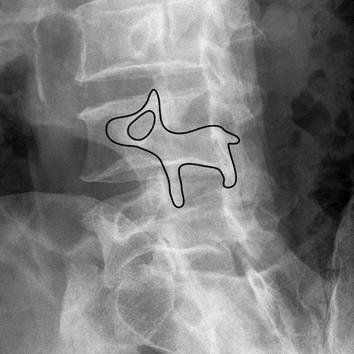

엑스레이에서는 측면으로 찍었을 때, scotty dog이라고 부르는 특징적인 모양을 찾게 됩니다.

요추마다 멍멍이처럼 생긴 부위가 있는데요. 이 멍멍이의 목이 끊어지면(!) 척추 분리증으로 진단하게 됩니다.